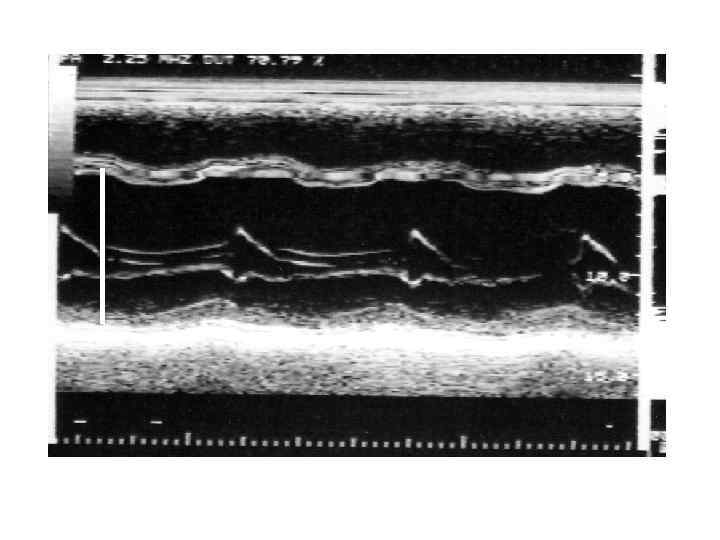

Рестриктивная кардиомиопатия Клиника и диагностика • Первичный амилоидоз • - Диагностика Моноклональная иммуноглобулинопатия – 90 % б-х Гипогаммаглобулинемия Плазмацитоз в костном мозге > 50% б-х Тромбоцитоз - 10% б-х На ЭКГ – «псевдоинфарктные изменения» , нарушения сердечного ритма и проводимости На ЭХОКГ – утолщение стенок левого и правого желудочка, утолщение эндокарда клапанов, регургитация, жидкость в перикарде, расширение предсердий, выраженное нарушение расслабления

Рестриктивная кардиомиопатия Клиника и диагностика • Первичный амилоидоз • - Диагностика Моноклональная иммуноглобулинопатия – 90 % б-х Гипогаммаглобулинемия Плазмацитоз в костном мозге > 50% б-х Тромбоцитоз - 10% б-х На ЭКГ – «псевдоинфарктные изменения» , нарушения сердечного ритма и проводимости На ЭХОКГ – утолщение стенок левого и правого желудочка, утолщение эндокарда клапанов, регургитация, жидкость в перикарде, расширение предсердий, выраженное нарушение расслабления